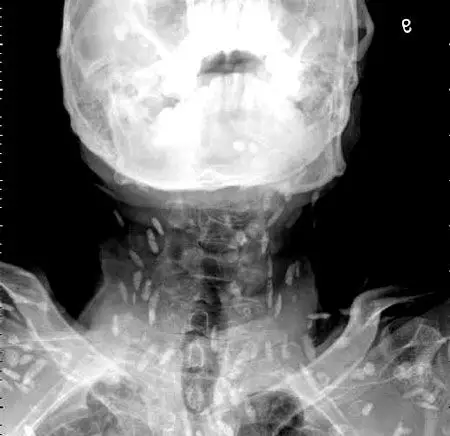

囊虫病全身皮下多发囊尾蚴